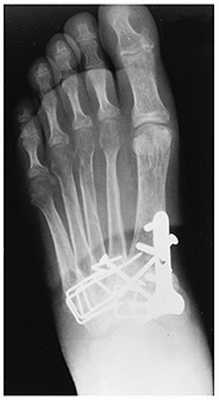

(Справа) Этому же пациенту были выполнены открытая репозиция и внутренний остеосинтез. При рентгенографии среднего отдела стопы в передне-задней проекции видно, что для обеспечения стабильности суставов требуется фиксация множества костей. Следует отметить наличие винта, который выполняет функцию поврежденной связки Лисфранка.

Открытое вправление вывиха, трансартикулярная фиксация 1-2-3 предплюсне-плюсневых суставов винтами.